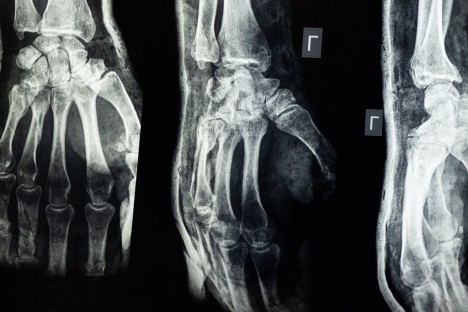

A hipermobilitás az ízületeinket tekintve azt jelenti, hogy végtajaink, testrészeink nagyobb mozgástartományban képesek mozogni, mint más embereknél. Gondolom, mindenki előtt ott van a kép, amikor a cirkuszi tornászok kitekerik magukat minden irányba, mintha gumiból lennének. Ők azok általában (nem minden esetben), akiknek az izmai és ízületei lazábbak, ezt pedig remekül tudják kamatoztatni. Ám amikor ehhez a fajta lazasághoz fájdalom és egyéb más panaszok társulnak, akkor beszélünk magáról a hipermobilitási szindrómáról.

Klassz trükknek tűnik, amikor az ember mondjuk a mutatóujját addig tudja hajlítani, hogy vissza tudja forgatni a kézfejére. Pedig ez egy idő után kellemetlen tünetekkel jár együtt, amik sajnos nem lesznek ennyire trükkösek. A hipermobilitási szindróma tünetei lehetnek terhelés után jelentkező fájdalmak, gyorsabb ütemű izomfáradékonyság, gyakori ficamok, rándulások, és például az a nyugtalanító kattogás, amikor ropognak az ujjaink. Ide sorolhatjuk a különböző hát- és derékfájdalmak egy részét, alvászavarokat, szív- és érrendszeri panaszokat, sőt, még az IBS-t, azaz az irritábilis bél szindrómát is.

Diagnózist felállítani nem lehet általában egyik pillanatról a másikra. Először mindig nézni kell egy kórelőzményt, hogy mióta áll fenn probléma, és nem okozhatta e ezt például egy rosszul gyógyult sérülés. Az orvos egy úgynevezett Brighton-skálát használva méri fel az ízületek lazaságának mértékét. Ez a skála 9 pontból áll, ahol egyes testrészeinket vizsgálják, hogy mennyire hajlékony a mozgásuk. Amennyiben ebből a 9 pontból legalább négy pontot érünk el, akkor már sejthető, hogy HMS áll a héttérben.